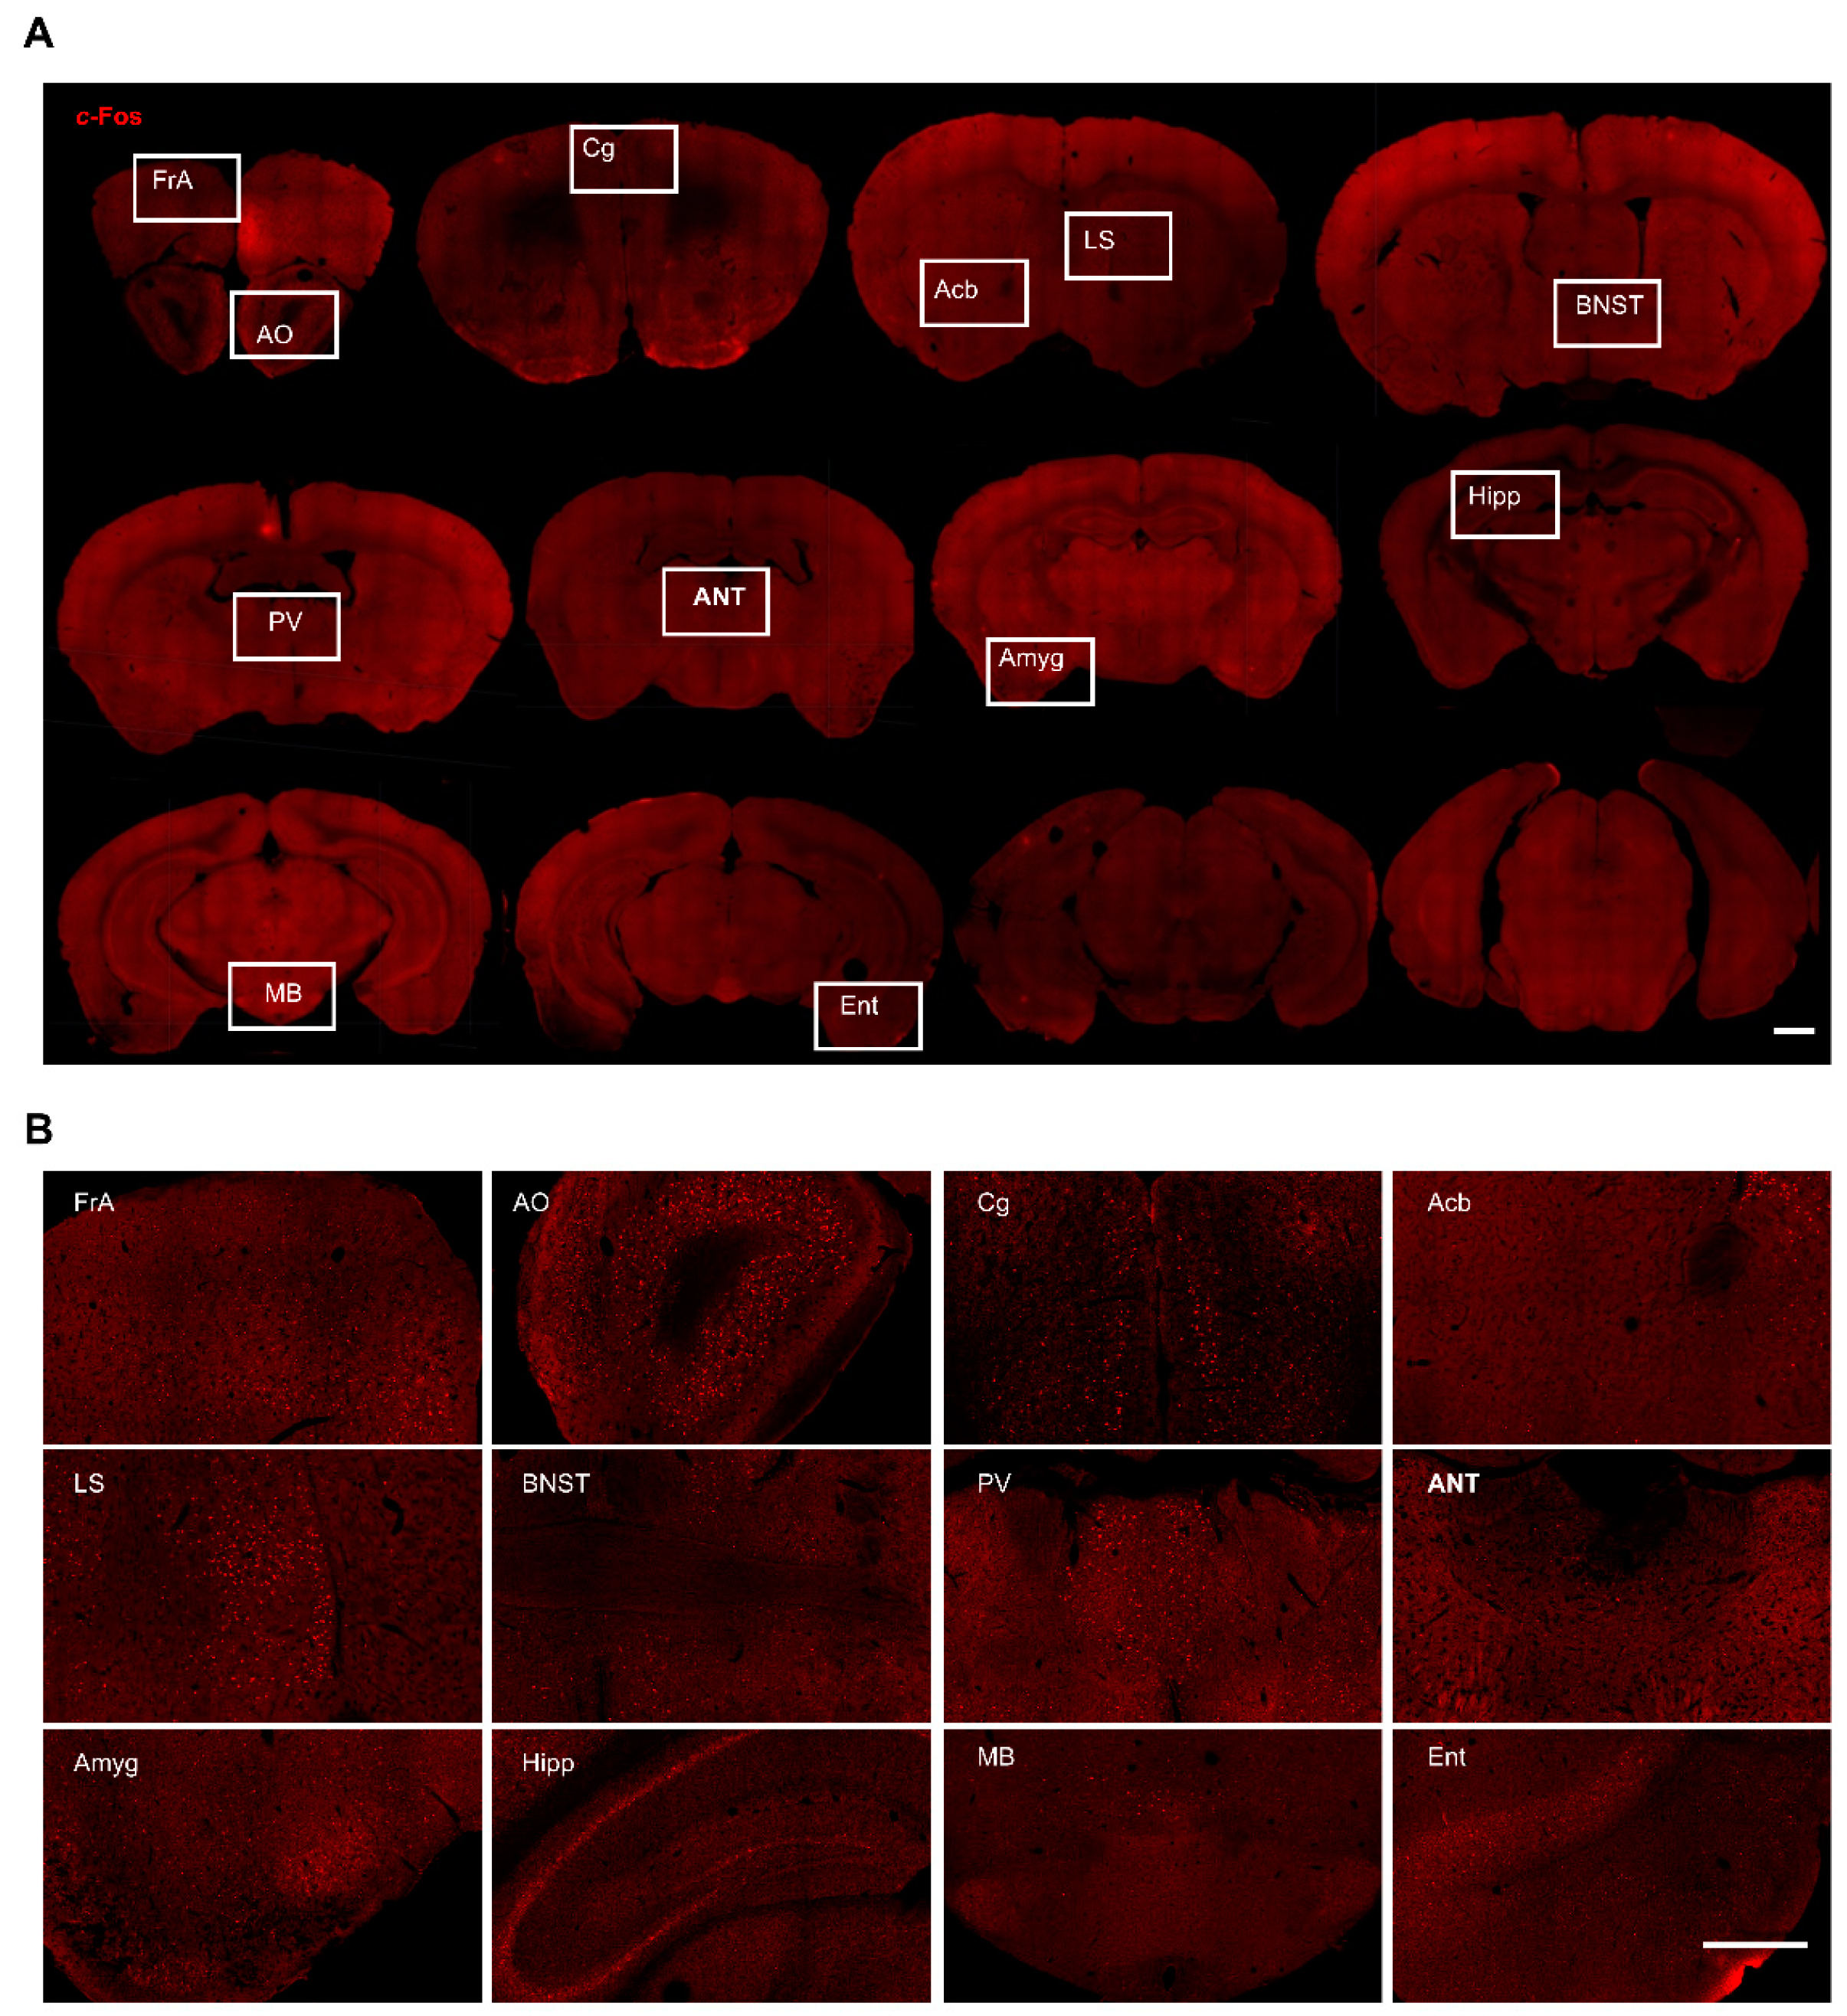

3. Results

3.1. c-Fos Expression in the Hippocampus

3.2. c-Fos Expression in the Cortices

3.3. c-Fos Expression in the Subcortical Regions

3.4. c-Fos Expression in the Thalamic Nuclei

3.5. c-Fos Expression in the Hypothalamic Nuclei